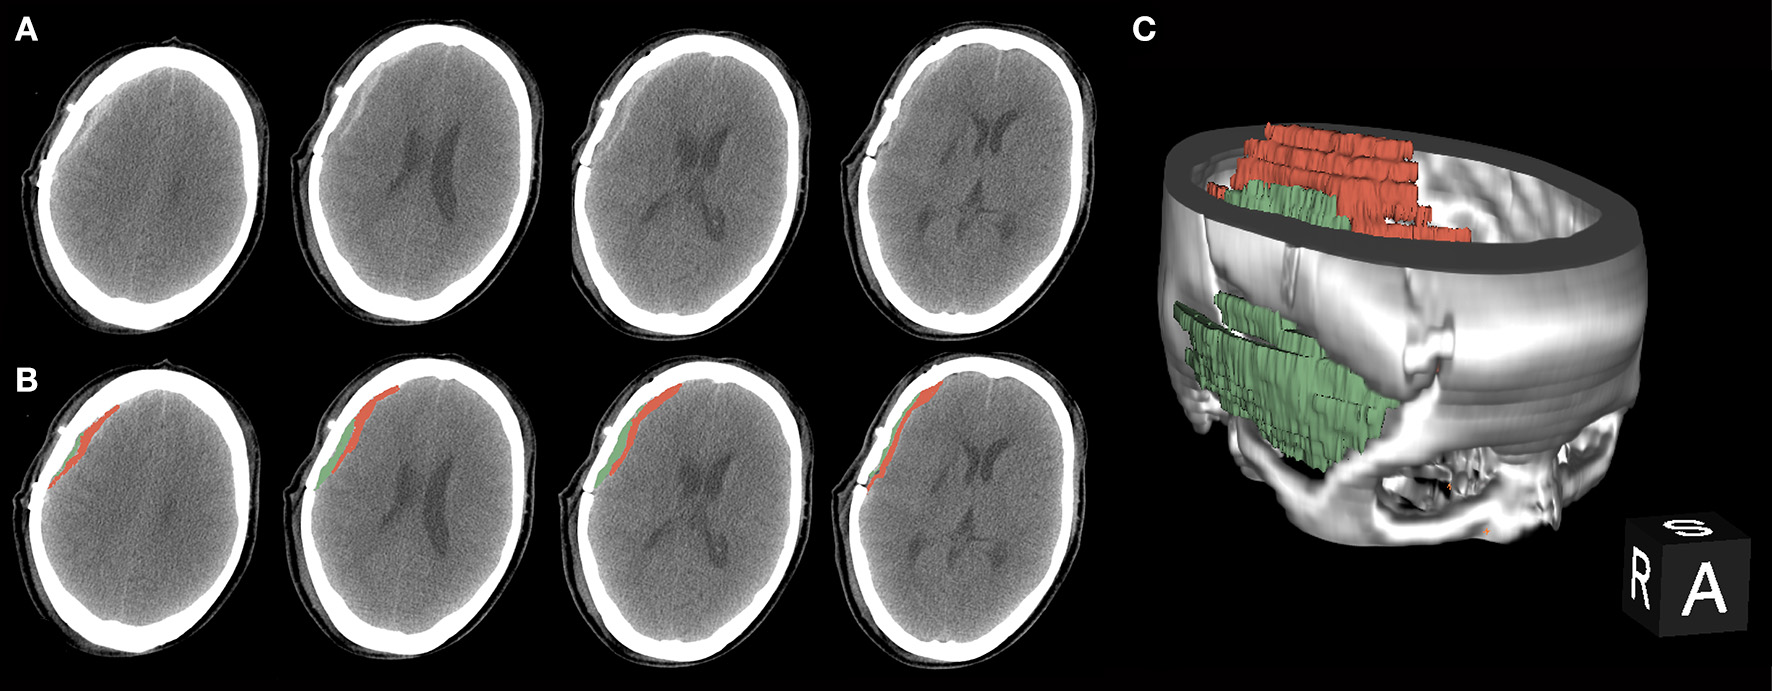

Bloody fluid volume was calculated using 3D Slicer software (https://www.slicer.org/) after performing CT or CTA within 3 days post-surgery (Figure 1). This software enables the measurement of intracranial hemorrhage more accurately than the conventional Tada formula (10). The calculated threshold range was set as the signal range of hematomas [i.e., 50–100 Hounsfield units (HU)]. The working process went as described previously (10). The separated temporal muscle showed slight high-density signal changes on CT in the acute post-operative stage, but the signal values of the muscles did not meet the abovementioned threshold range.

Figure 1

A procedure for typical bloody fluids around the operative area. (A) Original presentation of bloody fluids on post-operative computed tomography (CT) examinations. Black arrows indicate the separated temporal muscle. The graph shows different CT values with adjacent bloody fluids. (B) Bloody fluids are marked in red and the temporal muscle is marked in green using the 3D Slicer software. (C) The location of bloody fluids and the temporal muscle via 3D rebuilding.